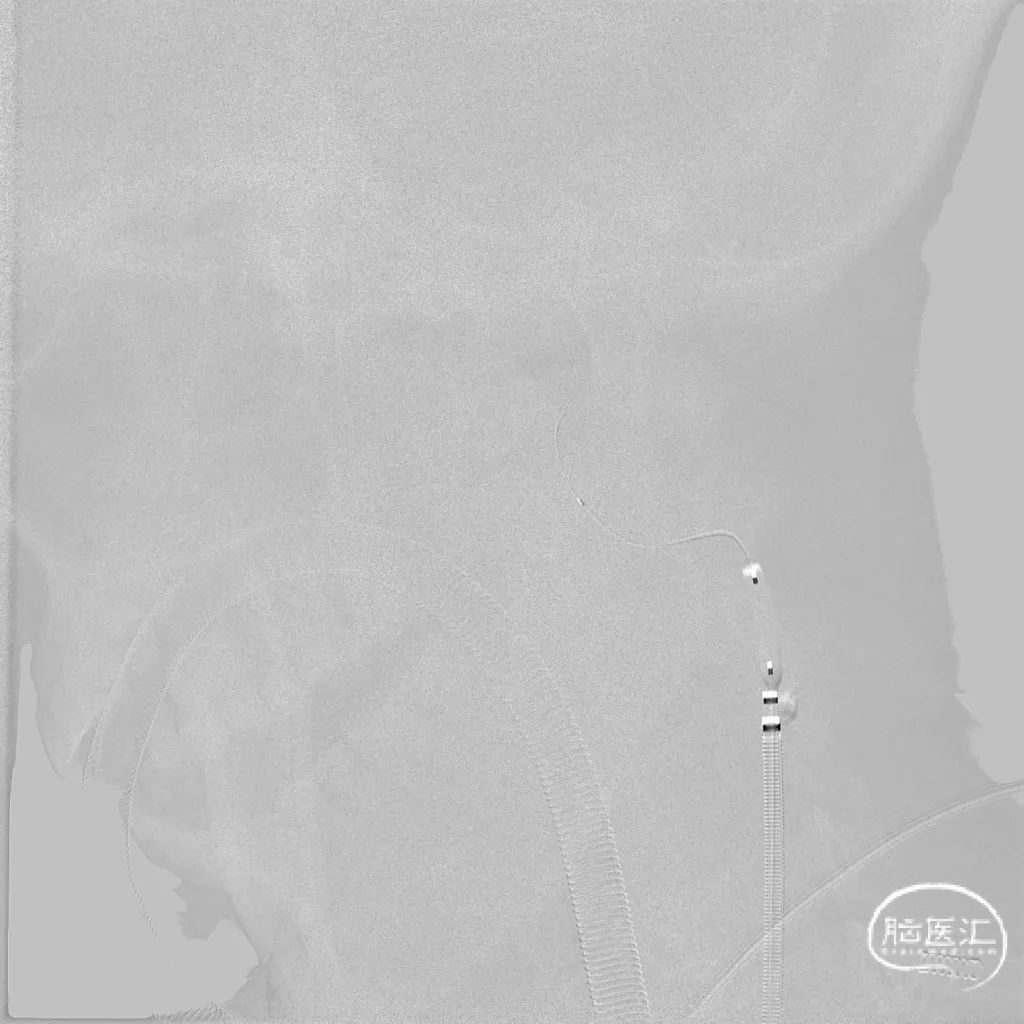

路图下,沿中间导管送入6mm保护伞至左侧颈内动脉C2段打开。

沿保护伞微导丝送入4*30mm 球囊至左侧颈内动脉起始部扩张, 复查造影示左侧颈内动脉起始部狭窄改善。沿保护伞微导丝送入7*50mm 自膨式颈动脉支架至左侧颈内动脉起始部-C1段,定位准确后释放,复查造影示架贴壁良好,前向血流通畅但流速稍慢。